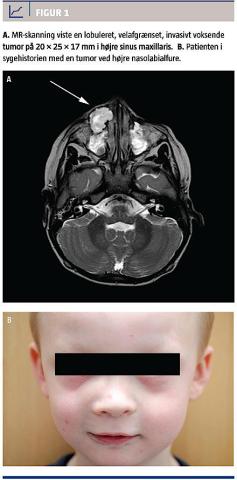

En treårig dreng havde haft en langsomtudviklet, uøm hævelse i højre nasolabialfure gennem syv uger. Hævelsen blev opdaget i forbindelse med infektion i højre øje. Drengen havde persisterende tåreflod og nasal sekretion. Han havde ingen almensymptomer og var tidligere rask, fraset dræn i trommehinden pga. sekretorisk otititis media.

Ved en objektiv undersøgelse fandtes en hård tumor i højre nasolabilafure med normal overliggende hud. Slimhinden var injiceret i højre cavum nasi. En øjenundersøgelse viste normale forhold, og den orale slimhinde og tænderne fremstod upåfaldende. Der blev foretaget MR-skanning (Figur 1) og CT. CT’en viste en invasivt voksende tumor med destruktion af højre maksil og infiltration af os nasale, det anteromediale orbitagulv, ductus nasolacrimalis og det anteriore tandanlæg 12.